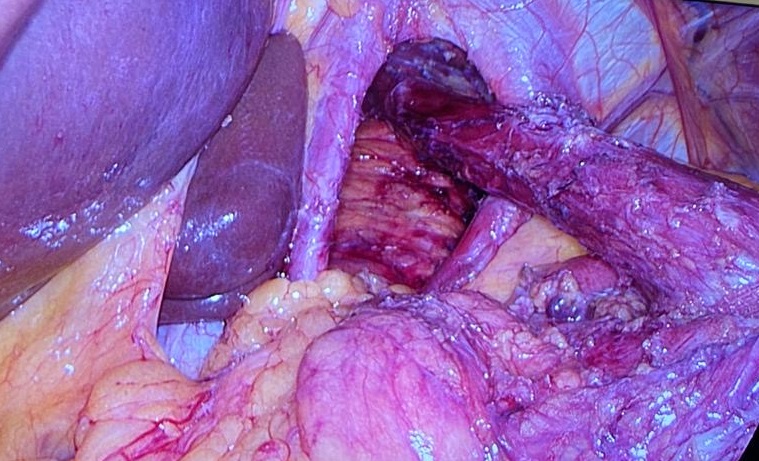

После компенсации водно-электролитных нарушений, стабилизации пациентки была выполнена плановая операция 11.01.20 г.: пластика диафрагмальной грыжи, задняя и передняя диафрагмокрурорафия, фундопликация по Ниссену. При ревизии обнаружено, что желудок полностью смещен в средостение через пищеводное отверстие диафрагмы и фиксирован там рубцово-спаечным процессом. В грыжевом мешке также располагаются поперечно-ободочная кишка и петля тонкой кишки. Ультразвуковыми ножницами рассечены спайки и рубцы. Поперечно-ободочная кишка, желудок низведены в брюшную полость. С помощью ультразвукового диссектора пересечены короткие желудочные сосуды, мобилизован свод пищевода, выделена его нижняя треть. Пищеводное отверстие дифрагмы расширено до 10 см (рис. 7).

Рис. 7. Мобилизованный пищевод и ножки диафрагмы